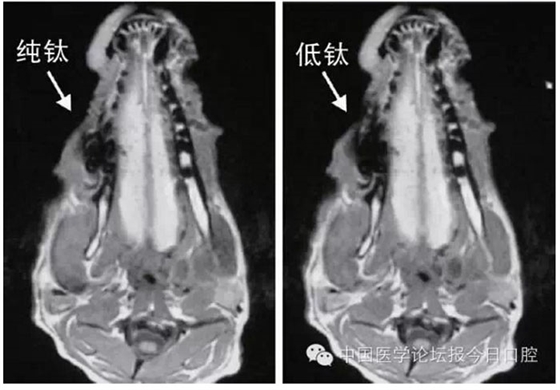

文獻研究中常使用的金屬包括鎳鉻合金、鈷鉻合金、低鈦合金、純鈦、金合金、金鈀合金、銀鈀合金等成分如表所示。大量研究得出近乎一致性的結(jié)論。金合金、金鈀合金、銀鈀合金對MRI影響甚微,與全瓷材料、丙烯酸樹脂極為相似,表現(xiàn)為修復(fù)體影像邊緣光滑、無變形、無偽影;純鈦金屬對MRI影響較小,接近于全瓷材料;但有的研究卻發(fā)現(xiàn)純鈦在核磁共振場中也產(chǎn)生偽影,但偽影涉及的掃描層數(shù)較少;低鈦合金(鈦合金)對MRI影響較大,介于純鈦和鎳鉻合金之間,中度偽影;鎳鉻合金、鈷鉻合金對MRI影響很大,鈷鉻合金更甚;表現(xiàn)為重度偽影、圖像扭曲變形(圖1、圖2)。不難看出,對MRI影響,全瓷材料、樹脂材料<金合金等貴金屬<純鈦<低鈦合金<鎳鉻合金<鈷鉻合金。有研究發(fā)現(xiàn)鈷鉻合金橋偽影大小與修復(fù)體長軸一致,影響范圍為固定橋近遠中徑2倍,頰舌徑的4倍;相同外形金屬修復(fù)體厚度增加,偽影增加。單個金屬樁核偽影可波及到上頜竇、牙槽骨、舌體、舌下腺等組織器官,但對眼底、眼內(nèi)容物、腦組織和頸椎成像基本無影響。

圖2 4種金屬冠在犬MRI檢查中的影響,圖片引自《實用口腔醫(yī)學(xué)雜志》2014第30期《4種金屬冠對磁共振成像影響的對比研究》一文,作者高嵐等